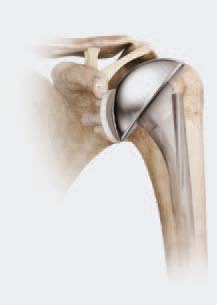

Schulterendoprothesen: Endoprothetik der Schulter bei schmerzhafter Schulterarthrose

Bei schweren Schäden an beiden Gelenkflächen kann eine Totalendoprothese (TEP) der Schulter erforderlich sein: Beide Gelenkflächen werden ersetzt und die oberarmseitige Prothesenkomponente wird im Markraum des Knochens verankert. © Depuy-Synthes

Nach schweren Frakturen des Schultergelenks oder nach Schulterarthrose ist die schmerzfreie Beweglichkeit der Schulter manchmal vollständig zerstört. In diesen Fällen kann eine Schulterprothese die Beweglichkeit wiederherstellen und den Patienten zu Schmerzfreiheit verhelfen.

Die Haltbarkeit der Schulterendoprothese ist sehr gut, da das Schultergelenk nicht zu den gewichttragenden Gelenken gehört wie zum Beispiel Hüfte oder Knie.

Röntgenbild einer Hemiprothese der Schulter, die den Oberarmkopf wie eine Kappe überkront. © Depuy-Synthes

Auch für leichtere Formen der Schulterarthrose gibt es angepasste Lösungen: Wenn eine Gelenkfläche, z. B. das Schulterblatt, noch eine intakte Knorpelschicht aufweist, ist der Einsatz einer Teilprothese (Hemiprothese) möglich. Bei der Teilprothese der Schulter wird der Oberarmkopf nur überkront. Die Gelenkfläche des Schulterblatts bleibt erhalten.

Häufige Patientenfragen zu Schulterschmerzen an Prof. Dr. Sven Ostermeier von der Gelenk-Klinik Freiburg

Die Oberarmkopffraktur wird in vielen Fällen durch Ruhigstellung behandelt. Wenn die Bruchstücke verschoben sind, muss eine Operation den Knochenbruch versorgen. Bei Fraktur mit Beteiligung der Gelenkflächen kann eine Schulterprothese notwendig werden.